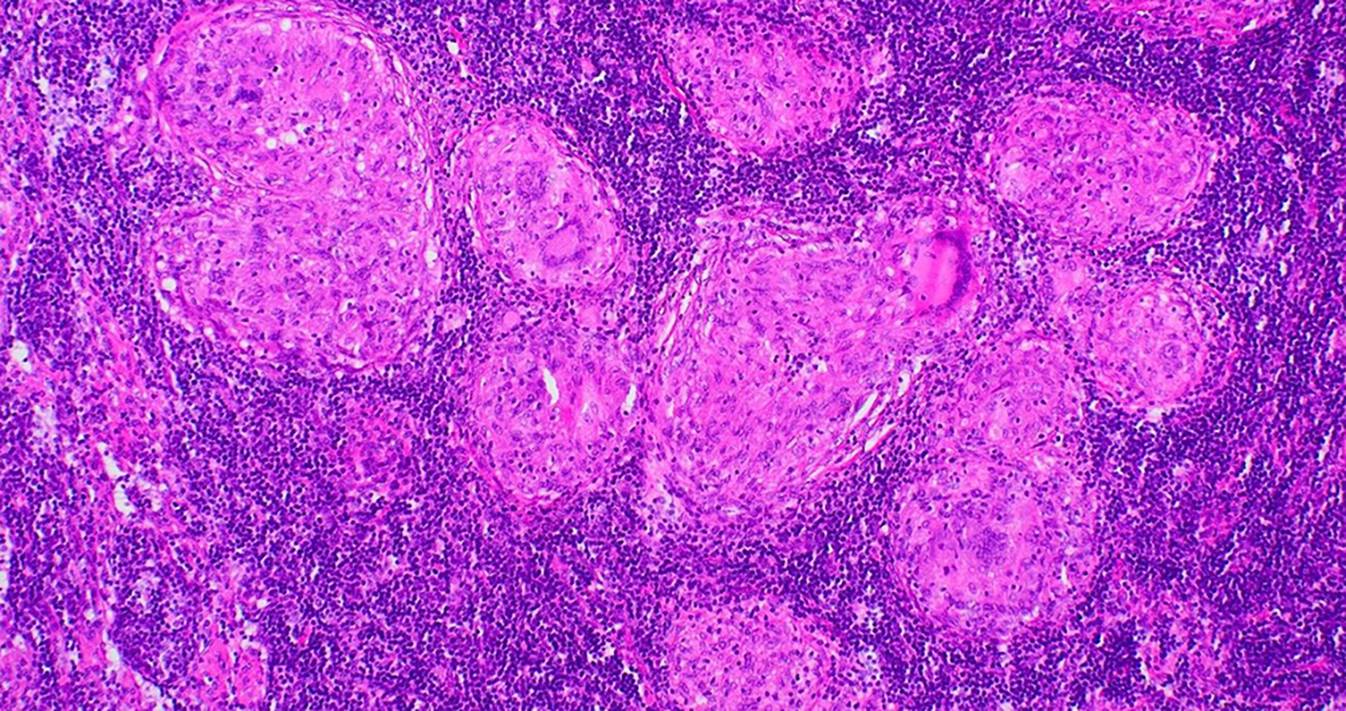

Die Sarkoidose ist eine Systemerkrankung letztlich unklarer Ursache, die zur Bildung von nichtverkäsenden Epitheloidzellgranulomen (Abb. 1) in verschiedenen Organen führt.

Abb. 1

Mehrere typische Epitheloidzellgranulome. Man sieht den „Randwall“ aus kleinen Lymphozyten, die Epitheloidzellen und teils zentrale Einschlüsse, aber keine Nekrose. (HE-Färbung, Vergrößerung 10:1)